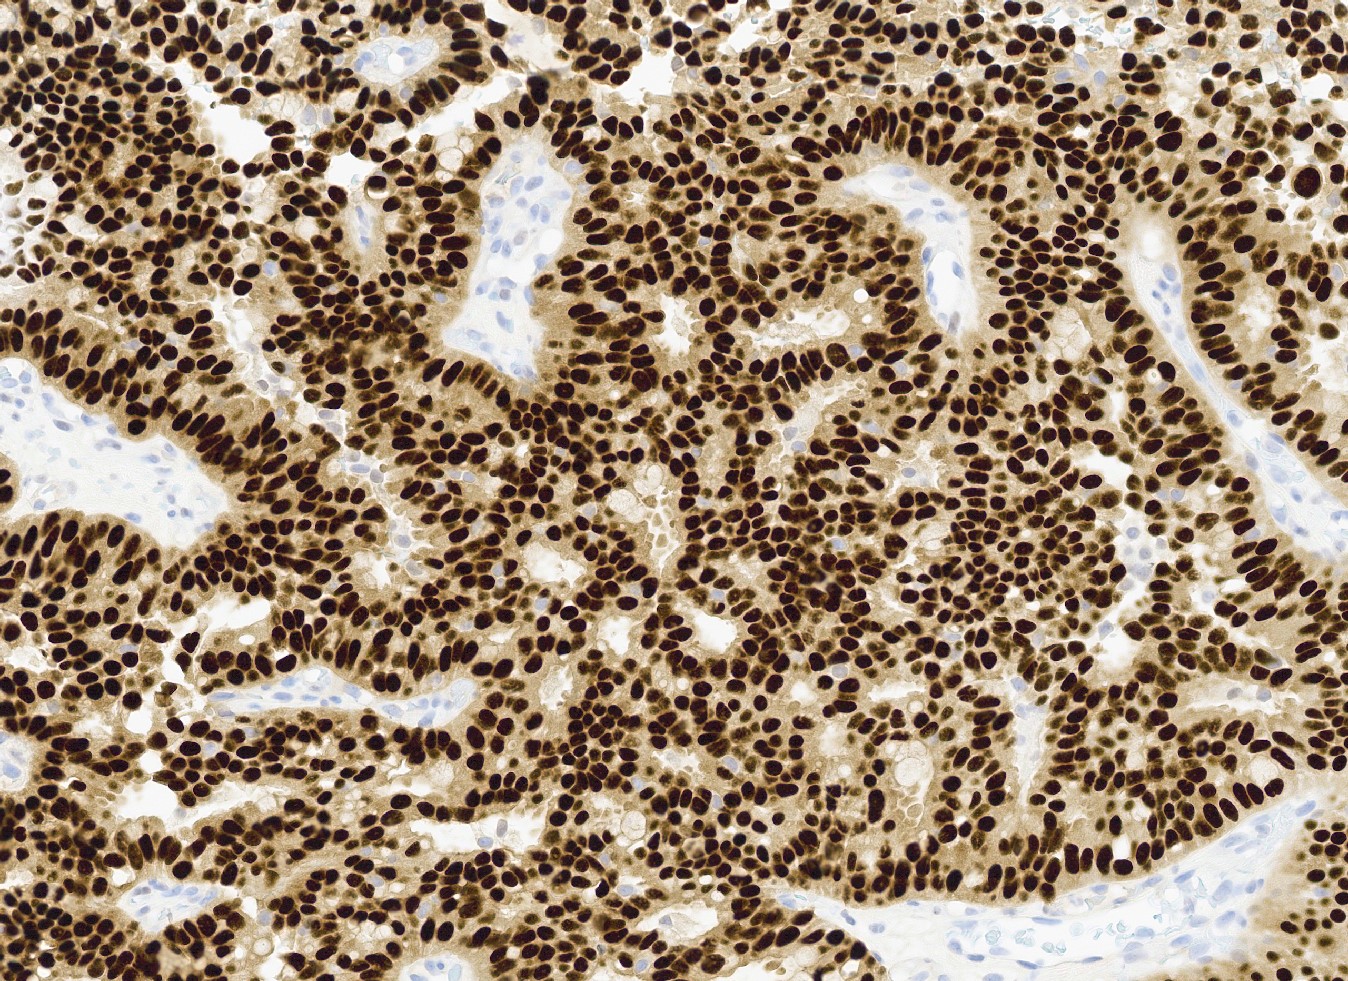

Positive stains

- ER and PR (strong, diffuse) (Curr Probl Cancer 2018;42:291, Mod Pathol 2021;34:1044)

Microscopic (histologic) images

Contributed by Kristen E. Muller, D.O. , Mariel Molina Nunez, M.D. and Julie Jorns, M.D. (Case #518)